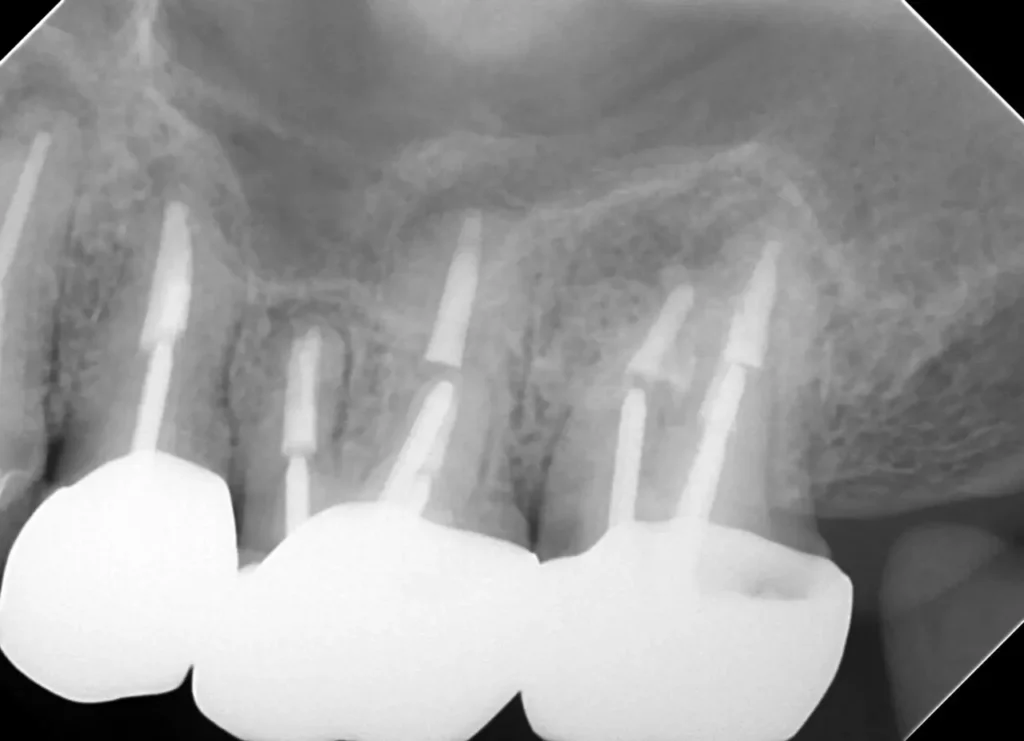

初診時レントゲン写真

インプラント隣の歯の根の先に人工材料が逸出しています。

初診時レントゲン写真2

右側(向かって左)の歯は以前、他院で外科的歯内療法を受けています